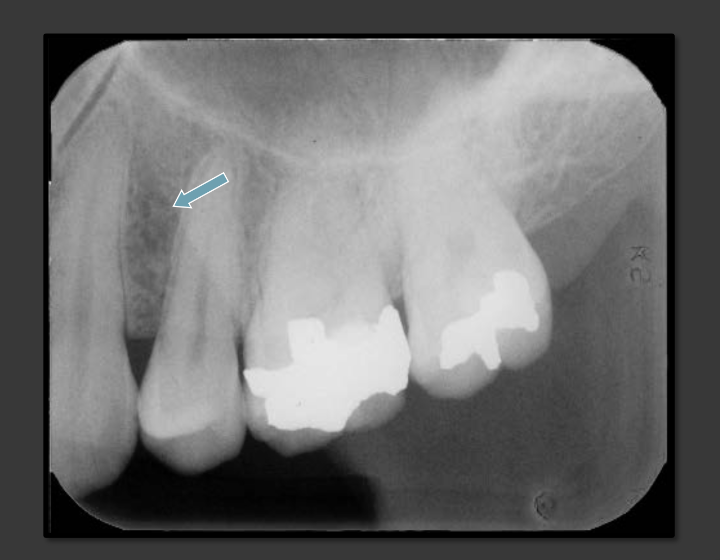

How does the lateral fossa present in a radiograph?

It is a radiolucency that appears in the bone that can surround the canine, lateral, and central.